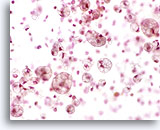

Microfagen

Patiënten waarbij schade in de microvasculatuur van de long optreedt ontwikkelen longbloedingen, die zich manifesteren door hemosiderine bevattende macrofagen